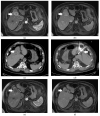

Surgical resection remains the cornerstone of curative treatment for intrahepatic cholangiocarcinoma (iCCA), but this option is only available to a small percentage of patients. For patients with unresectable iCCA, systemic therapy with gemcitabine and platinum-based agents represents the mainstay of treatment; however, the armamentarium has grown to include targeted molecular therapies (e.g., FGFR2 inhibitors), use of adjuvant therapy, liver transplantation in select cases, immunotherapy, and locoregional liver-directed therapies. Despite advances, iCCA remains a challenge due to the advanced stage of many patients at diagnosis. Furthermore, given the improving options for systemic therapy and the fact that the majority of iCCA patients succumb to disease progression in the liver, the role of locoregional therapies has increased. This review will focus on the expanding role of interventional radiology and liver-directed therapies in the treatment of iCCA.